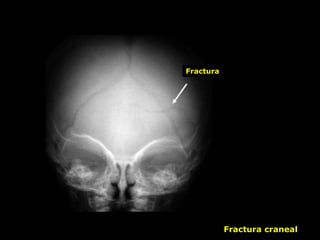

Lesiones Craneales

XXX

Hematoma

subgaleal

Fractura craneal y

hemorragia subdural

Fractura

Hemorragia Subaracnoidea

Fractura craneal